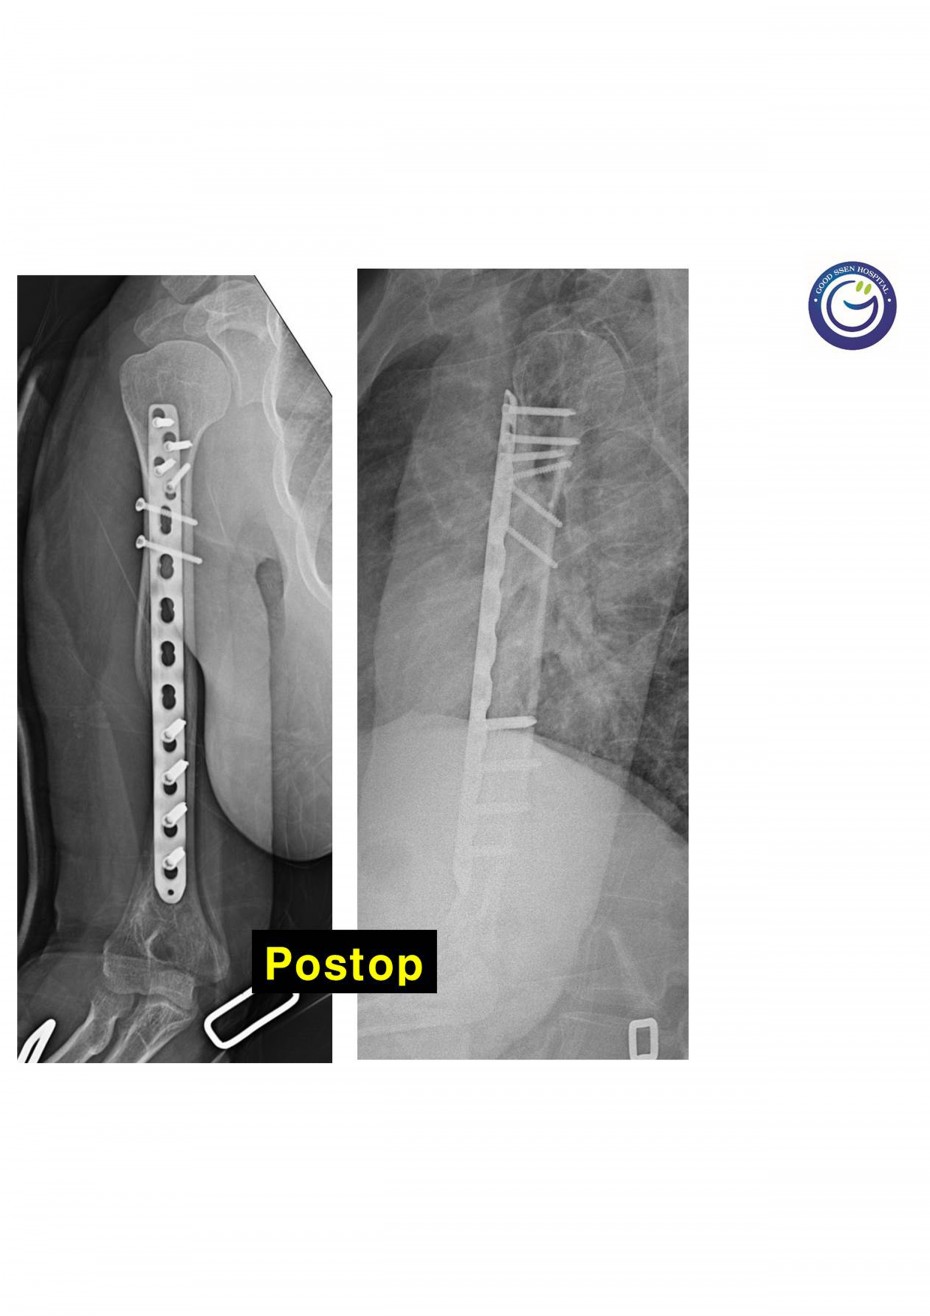

절개없이 고정하는 최소침습적 고정방법 (MIPO)